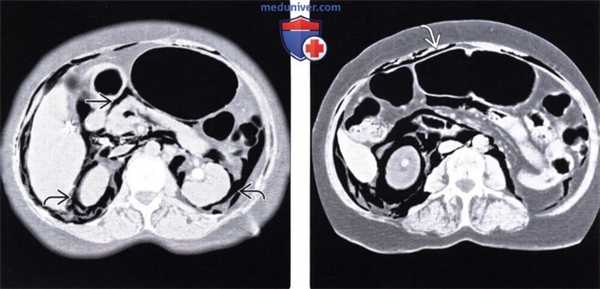

(Слева) При аксиальной КТ с контрастом у молодою человека, находящегося на ИВЛ после аварии на мотоцикле, выявлен напряженный пневмоторакс с правой стороны и малый пневмоторакс слева. Газ под давлением распространяется вдоль около-диафрагмальной жировой клетчатки.

(Справа) На аксиальном КТ срезе у этого же пациента визуализируется внепросветный воздух из грудной полости, распространяющийся в брюшную полость, очерчивающий контуры петель кишечника. Нет повреждения органов брюшной полости. (Слева) На аксиальном КТ срезе (с контрастным усилением) у пожилого пациента, находящегося на вентиляции легких под давлением, с документированным двухсторонним пневмотораксом и пневмомедиастинумом, визуализируется газ, распространяющийся под давлением в брюшную полость, забрюшинное пространство и брыжейку.

(Справа) На аксиальном срезе (КТ с контрастом) у этого же пациента в дополнение к обширному скоплению газа в забрюшинном пространстве визуализируется газ в брюшной полости. В подобных случаях газ может распространяться в кишечной стенке, симулируя пневматоз в результате ишемии.

(Справа) На аксиальном КТ срезе у этого же пациента визуализируется внепросветный воздух из грудной полости, распространяющийся в брюшную полость, очерчивающий контуры петель кишечника. Нет повреждения органов брюшной полости.

(Слева) На аксиальном КТ срезе (с контрастным усилением) у пожилого пациента, находящегося на вентиляции легких под давлением, с документированным двухсторонним пневмотораксом и пневмомедиастинумом, визуализируется газ, распространяющийся под давлением в брюшную полость, забрюшинное пространство и брыжейку.